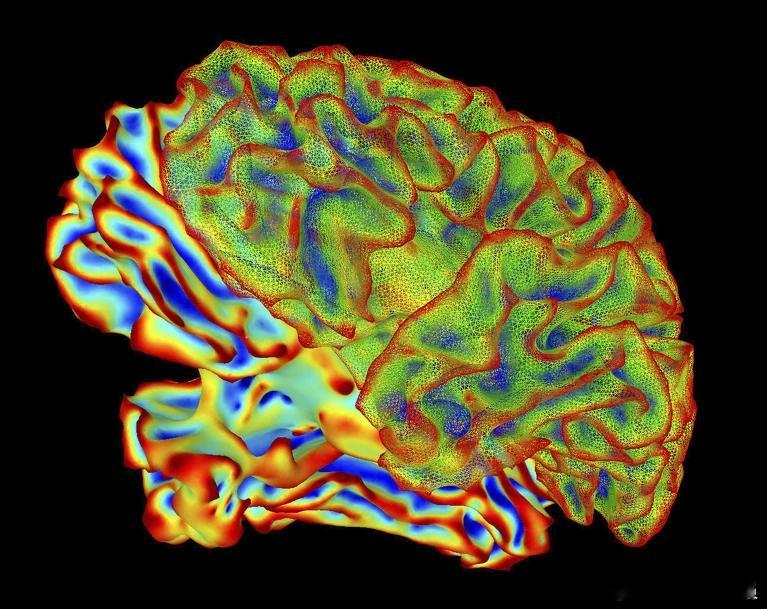

日本 NTT 通信科学实验室的计算神经科学家报告的这项“思维字幕”的新技术,能够利用大脑活动数据生成描述性句子,以极高的精确度捕捉人们眼前所见或心中所想的画面。

这项技术首先利用一个深度语言 AI 模型分析了超过 2000 段视频的文字描述,将每段视频转化为独特的数字“意义特征”。随后,研究者基于 6 名被试的大脑扫描数据对另一款 AI 进行训练,令其学会在他们观看视频时识别与每个意义特征相匹配的大脑活动模式。一旦训练完成,该大脑解码器便能读取一个人在观看视频时的新脑部扫描数据,并预测其含义特征。

由于这项技术采用的功能性磁共振成像是非侵入式手段,因此有望改善未来的脑机接口技术,更方便地将人类非言语思维表征直接转化为文本。